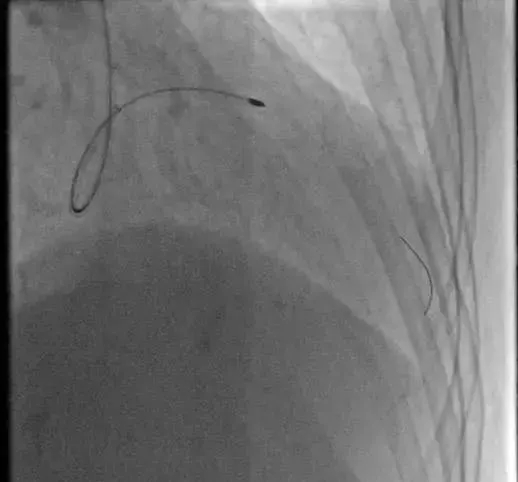

2018年8月31日,南昌市三医院心内一科冠脉介入团队为一例冠状动脉严重钙化狭窄的冠心病患者实施了冠脉旋磨术,成功植入冠脉支架。这是该院成功实施的首例冠脉旋磨治疗手术,目前此项技术在我省内仅有为数不多的几家医院可以独立开展,这标志着该院心内一科治疗复杂冠状动脉狭窄病变的技术步入新的里程。